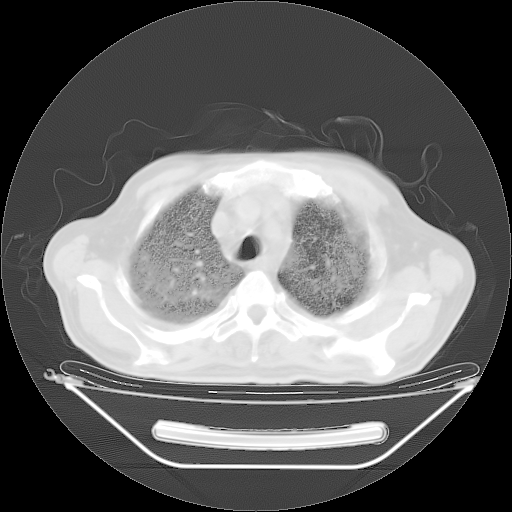

今天复查肺部CT,发现双肺广泛磨玻璃样改变。所以我把3月19日和5月9日相隔50天的肺部CT上传。请大家会诊。

2009年3月19日肺部CT片。

2009年3月19日肺部CT

胸腹部CT,诊断意见:左上肺叶钙化灶、左侧胸膜局限性增厚并钙化、胆囊炎。描述部分肺组织呈磨玻璃样改变。